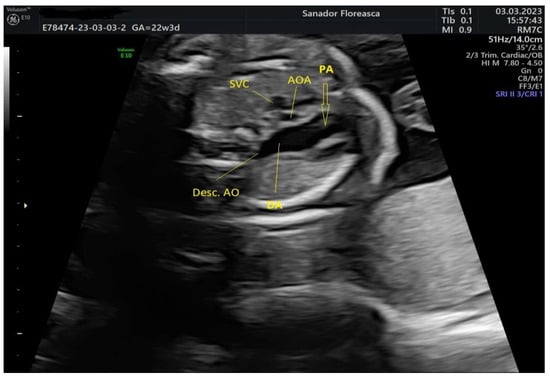

| Gestational age at cardiologic diagnosis | 22 weeks |

| Cardiologic diagnosis | IAA type B, malalignment-type VSD, pulmonary valve dyplasia, ARSA |